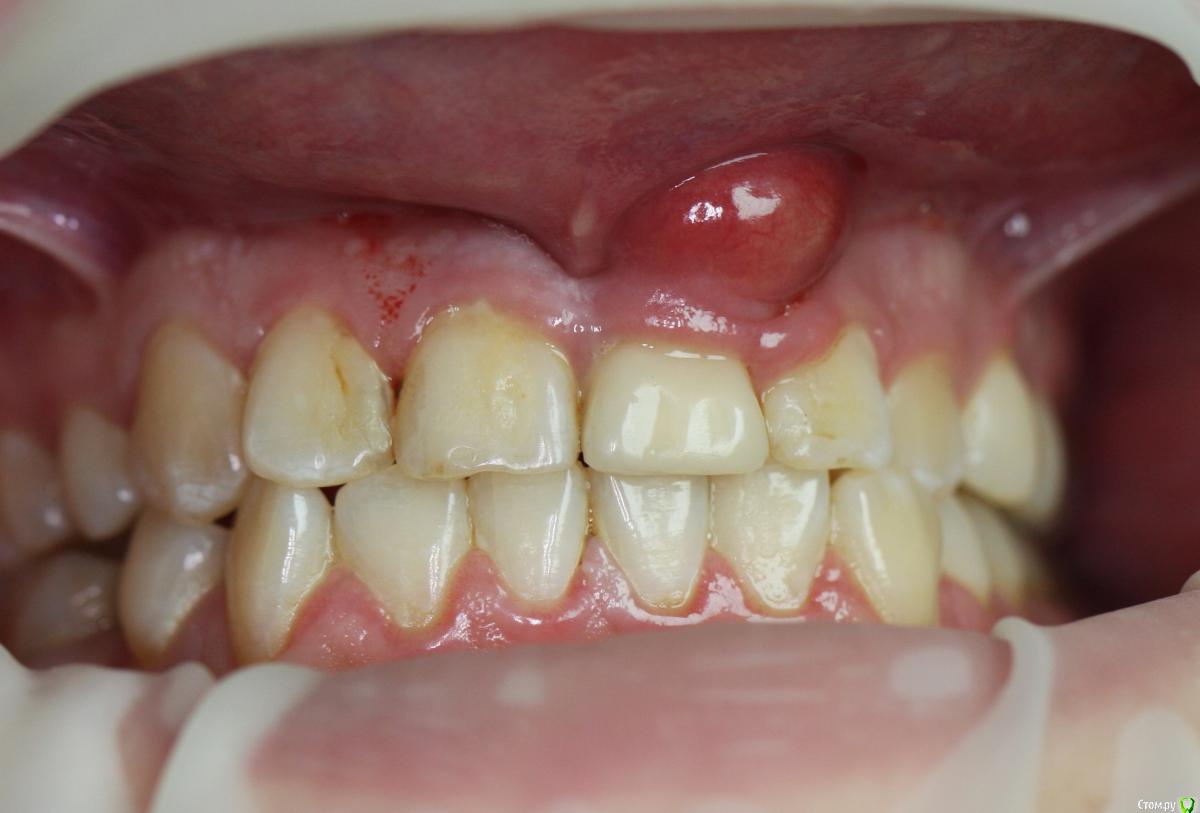

Zorrro Опубликовано 29 февраля, 2016 Автор Поделиться Опубликовано 29 февраля, 2016 (изменено) Через два дня пациент меня неприятно удивил.И ,безусловно,правильно было бы отменить операцию и ограничиться удалением,но… Вот такой был сюрприз под носом с нечищенными зубами.Обговорив риски,перекрестившись начали.Во время операции фото не делал.Слизистая в проекции 21 была сильно истончена острым гнойным процессом,буквально светилась.в итоге после эвакуации гноя промыл фурацилином,установил анкилос А11,подсыпал остеопласт вестибулярно и укрыл это всё сст из бугра в качестве мембраны.ещё один сст пошёл навременный абатмент в виде "шашлыка".Через 10 дней Через 4 месяцас рекомендацией замены пломбы на 12 у своего доктора мы ипопрощались.пациентка осталась глубоко удовлетворённой,а это главное. Изменено 29 февраля, 2016 пользователем Zorrro 4 Ссылка на комментарий